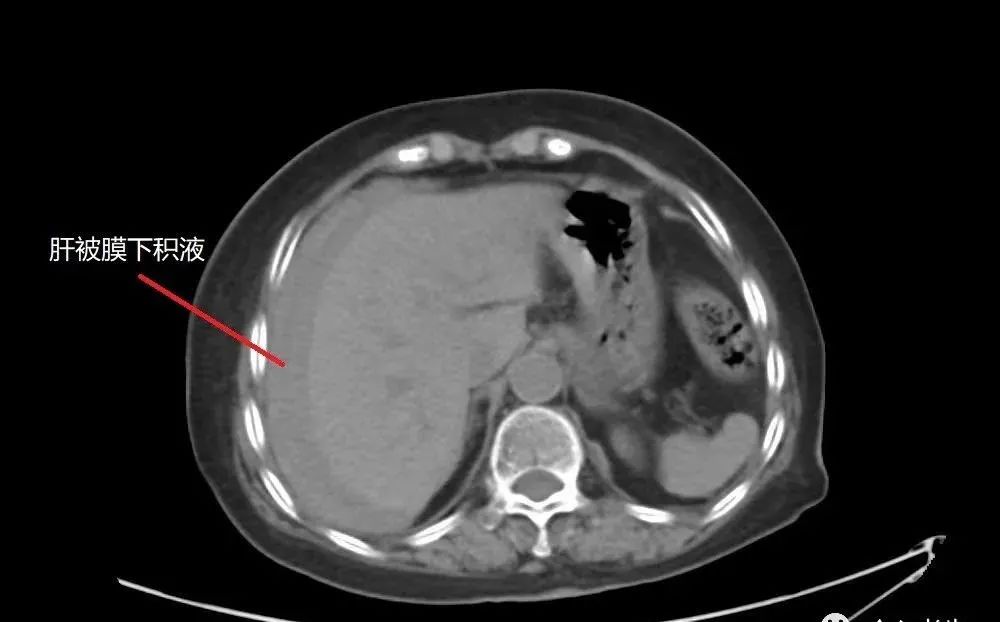

CT檢查發(fā)現

肝臟占位性病變

肝臟被膜下積血